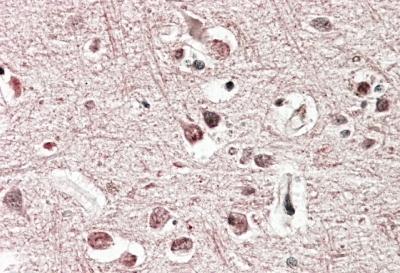

APR12293G (3.8 μg/ml) staining of paraffin embedded Human Cerebral Cortex. Steamed antigen retrieval with citrate buffer pH 6, AP-staining. |